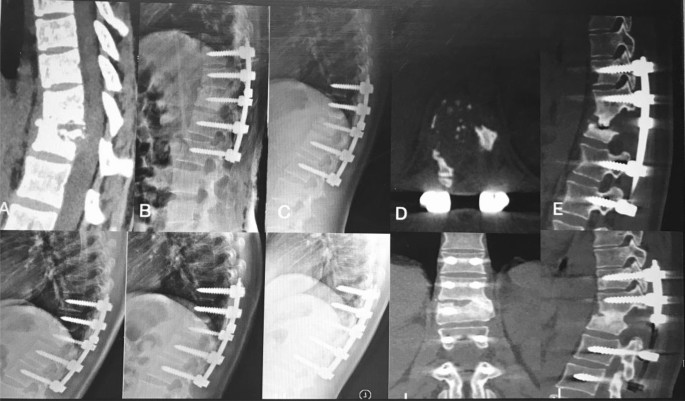

The thoracic spinal TB was well cured and all patients achieved bony fusion at a mean 12.90 ± 3.91 months. The mean angle of 24.35 ± 5.74° preoperatively showed a significant difference between 1 week postoperatively and final FU. Although there were the loss of angle at final FU comparing with the 1 week postoperatively, it still maintain the good alignment and the segmental stability (Figs. 3, 4). One case of rod fracture was observed 2 years postoperatively, and the revision surgery was performed with an iliac graft (Fig. 5). Some postoperative complications occurred, such as water-electrolyte imbalance (two cases) and superficial infection (two cases).

A 22-year-old female patient with thoracic spinal tuberculosis (T11–12) underwent posterior debridement and decompression combined with instrumentation. (A) Preoperative computed tomography (CT) shows bone destruction of the T11–12 vertebrae and compression of the spinal cord. (B–E) The 1-week and 6-month postoperative X-rays and 6-month postoperative CT show the correction was maintained, but the bone was not fully healed. (F,G) The 1-year and 2-year postoperative X-ray show the kyphosis correction had been lost. (H–J) At 5-year FU, plain X-ray and CT showed solid bone fusion.

A 51-year-old woman with thoracic spinal tuberculosis (T11–12) underwent posterior debridement and decompression combined with instrumentation. (A,B) Preoperative computed tomography (CT) shows bone destruction of the T11–12 vertebrae and compression of the spinal cord. (C,D) The 2-year postoperative X-ray and CT demonstrate the bone was unhealed, and a rod fracture was observed. (E–H) The revision surgery was performed with an iliac graft. X-ray and CT show the good location of the bone graft.